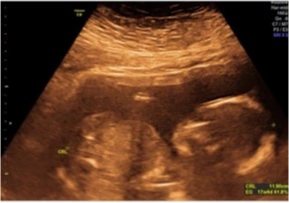

Ecografía Obstétrica

15 a 39 Semanas